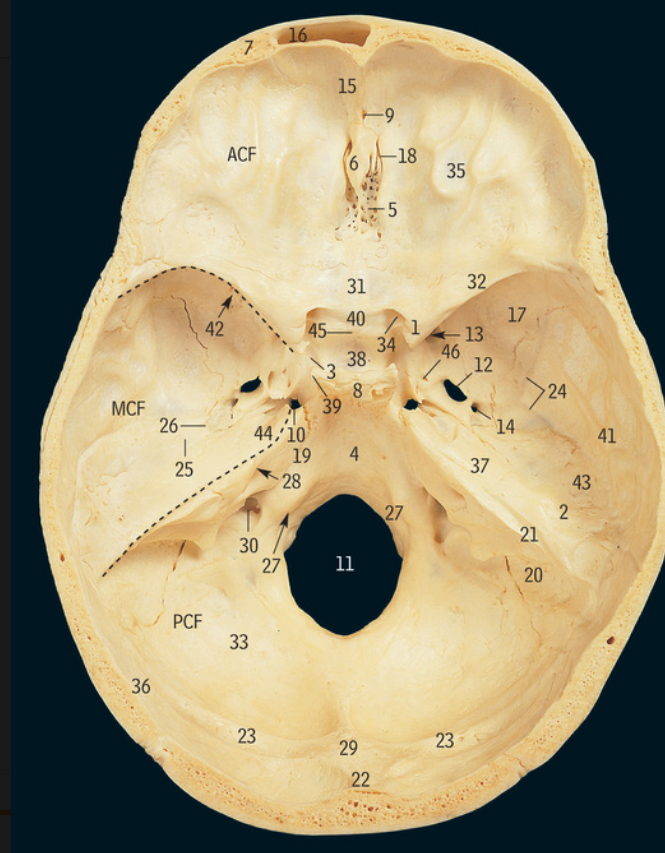

5

Cribiform plate

6

Crista galli

17

Greater wing of sphenoid bone

32

Lesser wing of sphenoid bone

38

Pituitary fossa

34

Optic canal

42

Superior orbital fissure

12

Foramen ovale

13

Foramen rotundum

14

Foramen spinosum

27

Hypoglossal canal

11

Foramen magnum

Supra-orbital notch

29

Occipital condyle

48

Superior nuchal line

Which part of the ethmoid bone does the olfactory nerve exit

Which part of the ethmoid bone does the falx cerebri attach

Which part of the frontal bone does the supra-orbital nerve travel through

What cranial nerves travel through the superior orbital fissure

CN III/3, IV/4, V1/ophthalmic, VI/6

What travels through the hypoglossal canal

Hypoglossal nerve

What travels through the formen magnum

Spinal cord, accessory nerve

What muscles attach to the superior nuchal line

Occipitalis and trapezius

37

Zygomatic process of temporal bone

What muscle attaches to the zygomatic process of the temporal bone

18

Mastoid processÂ

Petrous part of temporal bone

28

Internal auditory meatus

9

Mandibular fossa

3

Carotid canal

46

Styloid process

47

Stylomastoid foramen